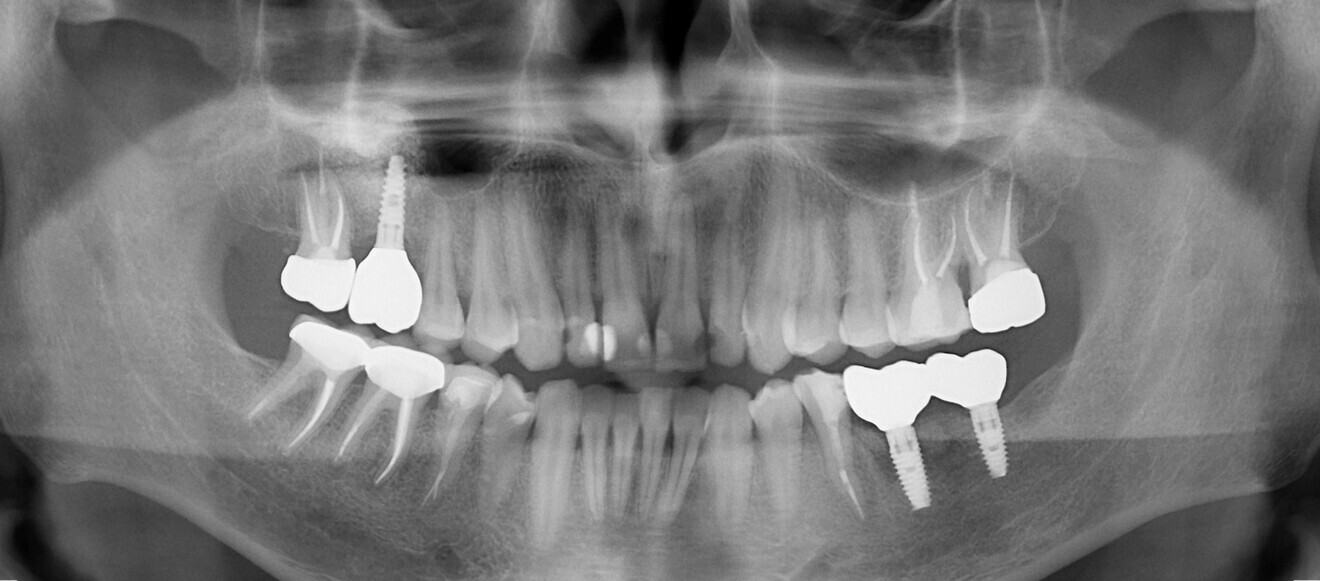

Fig. 20 : Radiographies prises en 2017.

Fig. 21 : Radiographie prise  en 2019.

Fig. 22 : Radiographie  prise  en 2022.